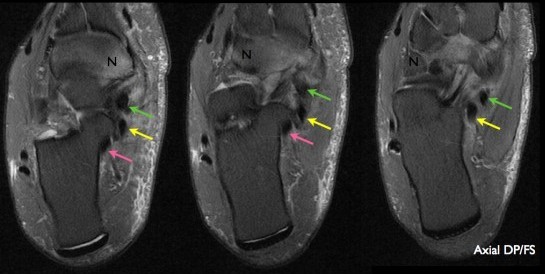

4. 어느 굴곡건 또는 내측건의 파열이 가장 흔한가?

후경골근건(PTT)이 내측 힘줄 파열에서 가장 흔하다. 이러한 파열은 중년 여성에서 자주 발생한다. 후경골근건 파열은 평발의 결과로 발생한다. 후경골근건 파열은 대개 힘줄의 부착부 근처에서 발생하고 부주상골(accessory navicular)이나 골극형 주상골(cornuate navicular bones)과 연관된다. 정상적으로 후경골근건(PTT)은 장지굴근건(FDL)이나 장모지굴근건(FHL)의 두 배 정도의 크기다. 만약 건막염(tenosynovitis)이나 힘줄이 크게 거대화 되었다면 후경골근건 파열을 의심해야만 한다. 후경골근건(PTT)과 장지굴근건(FDL)이나 장모지굴근건(FHL)의 크기 비교는 유용할 수 있다.

△ 후경골근건(초록색 화살표)의 거대화와 주상골(N)의 골수종

△ 정상적인 장지굴근건(노란색 화살표)과 장모지굴근건(분홍색 화살표)

(이미지 출처 : http://www.image-echographie.net/?r=1&ssr=51&a=890&langue=en)